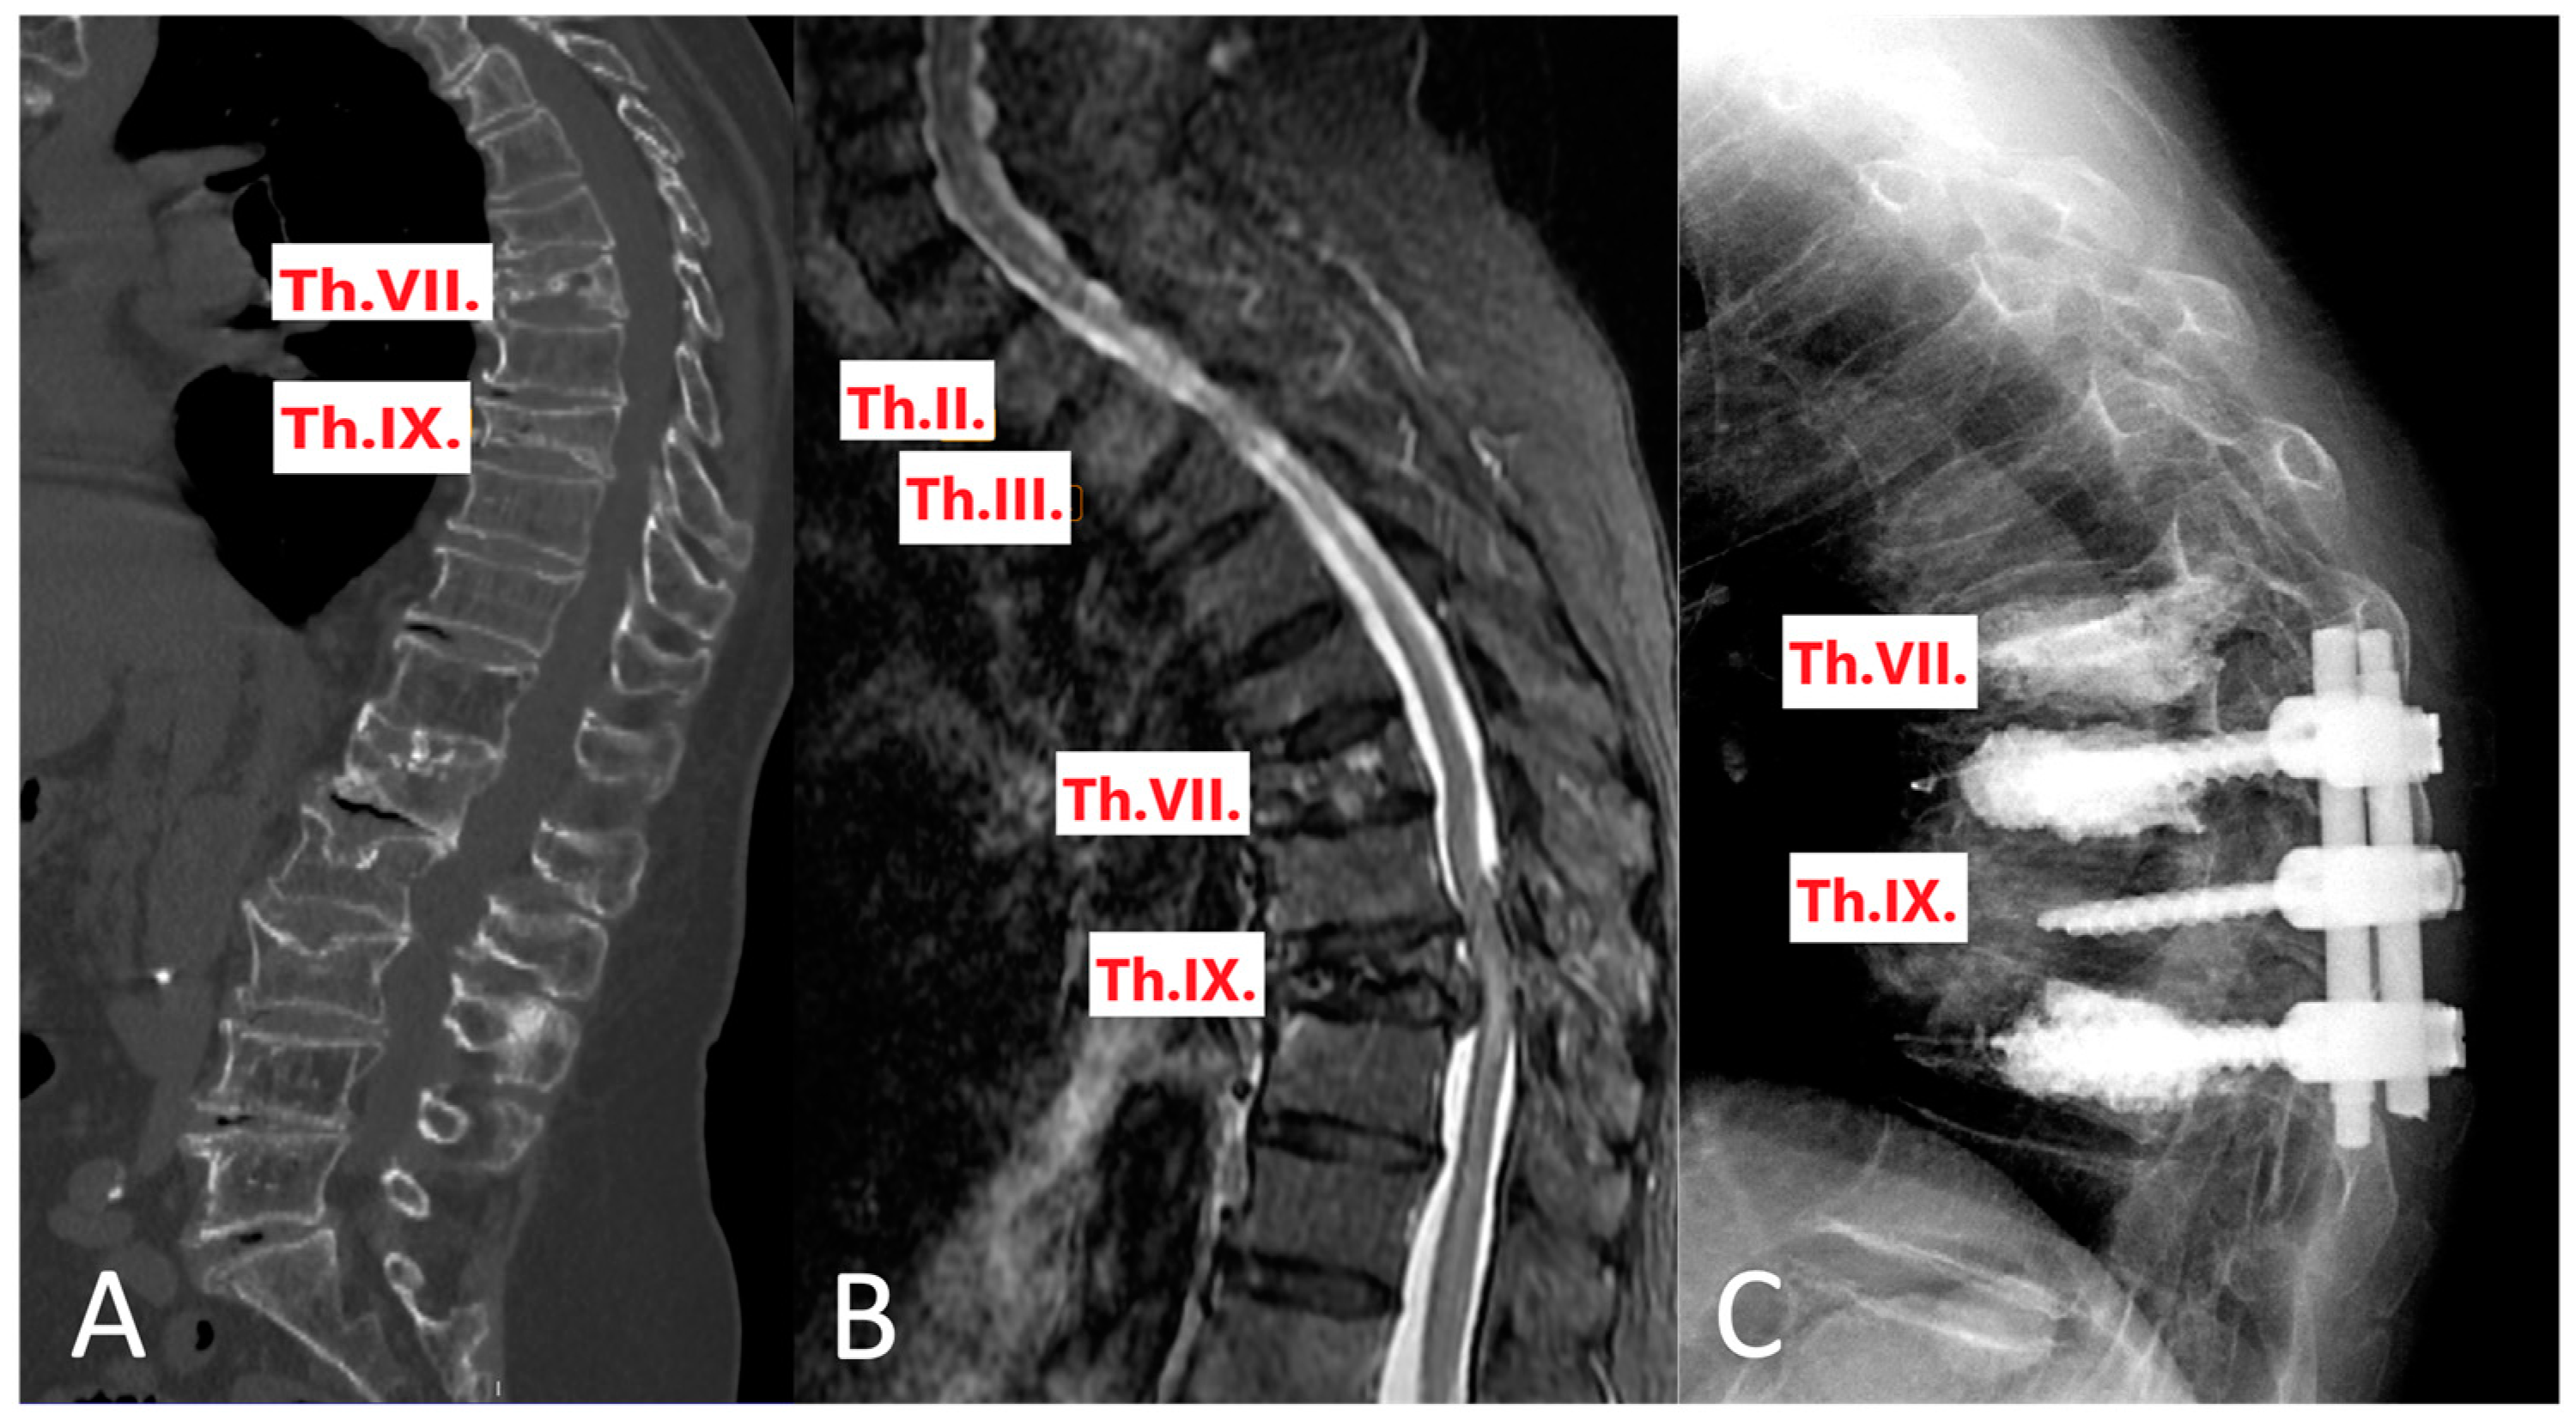

A notable case can be highlighted: A patient initially underwent a CT scan that identified fractures at the ThVII and ThIX vertebrae. However, subsequent STIR MRI imaging provided a more detailed assessment of the fracture types. Based on the CT findings, a long posterior spinal fixation was planned, from ThVII to ThX, accompanied by cementoplasty at ThVII and ThX. The STIR MRI revealed that the fracture at ThVII was only an AO1 type, where it was thought an AO3 type based on CT. Consequently, this led to a revised plan involving a shorter fixation range from ThVIII to ThX, while still proceeding with cementoplasty at ThVII and ThX (Figure 4).

Figure 4. Sagittal section views of a patient with multiple fractures and subsequent intervention. (A) CT scan, (B) STIR MRI, offering enhanced fracture detection, and (C) illustrating the intervention implemented following STIR MRI.